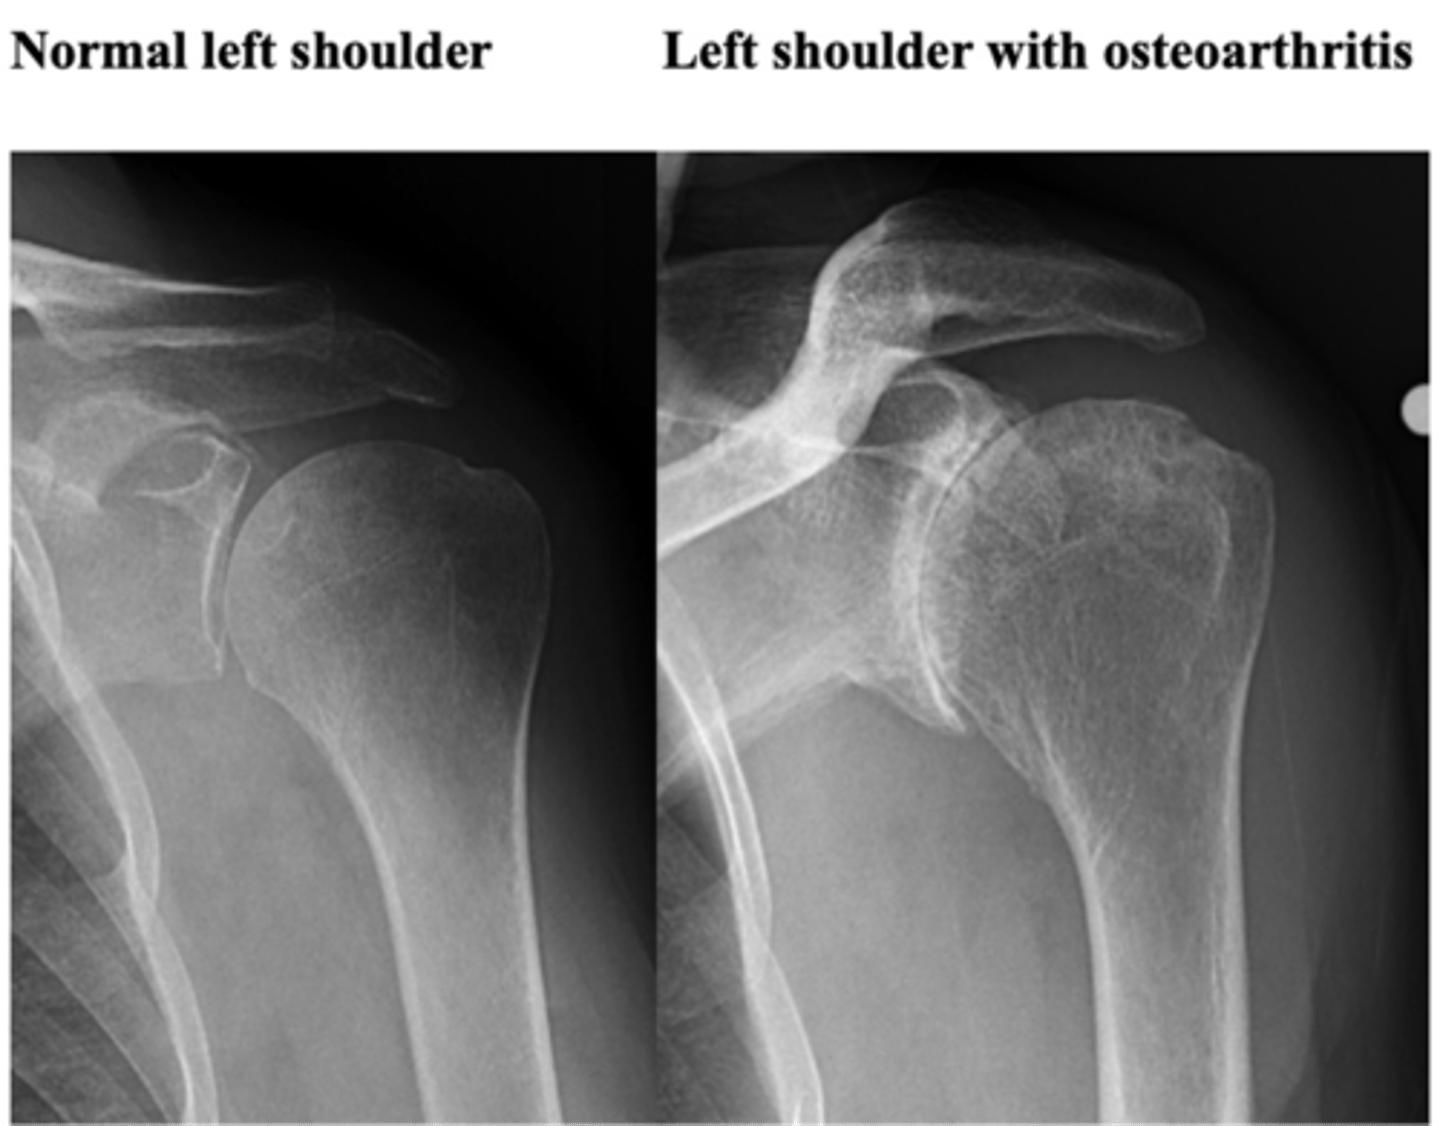

1. A (alignment) = osteophytes

2. B (bone density) = sclerosis

3. C (cartilage space) = loss of space

Which 3 MAIN things are you looking for when it comes to classifying OA?

GHJ OA w/ cystic changes of the glenoid fossa, which essentially means the bone tissue is starting to wear away --> concern when it comes to TSA

What is this image depicting? Why does it matter?